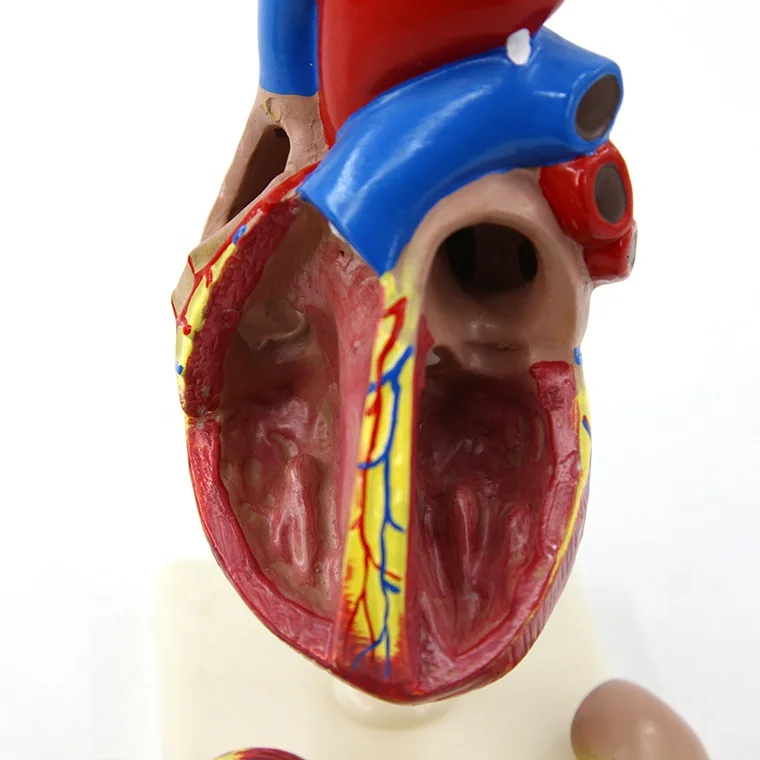

Valentine’s Day ช็อกโกแลตหัวใจ 12 ชิ้น – ของขวัญรังนกแท้ คอซซี่ โมเดลหัวใจมนุษย์ (Human Heart) | Shopee Thailand

โมเดลหัวใจมนุษย์ (Human Heart) | Shopee Thailand หัวใจมนุษย์ ภาพสต็อก – ดาวน์โหลดรูปภาพตอนนี้ – หัวใจ – อวัยวะภายใน …

ขยายกายวิภาคหัวใจมนุษย์รุ่น 3 ชิ้นส่วน – Buy กายวิภาคหัวใจ,หัวใจ … หัวใจมนุษย์ การออกแบบรายละเอียด ภาพประกอบสต็อก – ดาวน์โหลดรูปภาพตอนนี้ …

ForgetMeNot: Dessert strawberries with chocolate and cream | ช็อกโกแลต … ชีวิตพลาสติกกายวิภาคหัวใจมนุษย์รุ่น2ชิ้นส่วน – Buy การสอนรุ่น,Anatomy …

ชีวิตพลาสติกกายวิภาคหัวใจมนุษย์รุ่น2ชิ้นส่วน – Buy การสอนรุ่น,Anatomy … ช็อคโกแลตรูปหัวใจ [ภาพวาดฟรี] | OkusanPix

หัวใจวิทยาศาสตร์เรื่องกายวิภาคศาสตร์ทางการแพทย์หัวใจมนุษย์รุ่นขาย – Buy … รูปเวกเตอร์ฟรีหัวใจการ์ตูนปุ่ม PNG , หัวใจมนุษย์, หัวใจ, เซลล์ภาพ PNG …

ชีวิตพลาสติกกายวิภาคหัวใจมนุษย์รุ่น2ชิ้นส่วน – Buy การสอนรุ่น,Anatomy … ขนมช็อกโกแลตแท่ง ตรา โชกี้ โชกี้ 1 บาท แพ็ค 100 ชิ้น | Shopee Thailand

ขนมช็อกโกแลตแท่ง ตรา โชกี้ โชกี้ 1 บาท แพ็ค 100 ชิ้น | Shopee Thailand ชีวิตพลาสติกกายวิภาคหัวใจมนุษย์รุ่น2ชิ้นส่วน – Buy การสอนรุ่น,Anatomy …

ชีวิตพลาสติกกายวิภาคหัวใจมนุษย์รุ่น2ชิ้นส่วน – Buy การสอนรุ่น,Anatomy … รักสุดใจ! ช่อช็อกโกแลตให้เธอ รวมไอเดียช่อช็อกโกแลตสื่อรัก มอบให้แฟน

รักสุดใจ! ช่อช็อกโกแลตให้เธอ รวมไอเดียช่อช็อกโกแลตสื่อรัก มอบให้แฟน แบบจำลองหัวใจมนุษย์ขนาดชีวิตที่มีสีพื้นโปร่งใสโรคหัวใจทางการแพทย์แบบ …

แบบจำลองหัวใจมนุษย์ขนาดชีวิตที่มีสีพื้นโปร่งใสโรคหัวใจทางการแพทย์แบบ … Chocolate Heart, Hand-drawn sketch Chocolate s, brown, food png | PNGEgg

Chocolate Heart, Hand-drawn sketch Chocolate s, brown, food png | PNGEgg แบบจำลองหัวใจมนุษย์ขนาดชีวิตที่มีสีพื้นโปร่งใสโรคหัวใจทางการแพทย์แบบ …

แบบจำลองหัวใจมนุษย์ขนาดชีวิตที่มีสีพื้นโปร่งใสโรคหัวใจทางการแพทย์แบบ … ช็อกโกแลต รูปฟุตบอล เหรียญทอง หัวใจ บรรจุ 60 ชิ้น | Shopee Thailand

In-306 3d กายวิภาคศาสตร์หัวใจมนุษย์รูปแบบทางการแพทย์พลาสติกกายวิภาค … หัวใจมนุษย์ ภาพสต็อก – ดาวน์โหลดรูปภาพตอนนี้ – หัวใจ – อวัยวะภายใน, การ …

หัวใจวิทยาศาสตร์เรื่องกายวิภาคศาสตร์ทางการแพทย์หัวใจมนุษย์รุ่นขาย – Buy … หัวใจวิทยาศาสตร์เรื่องกายวิภาคศาสตร์ทางการแพทย์หัวใจมนุษย์รุ่นขาย – Buy …

หัวใจวิทยาศาสตร์เรื่องกายวิภาคศาสตร์ทางการแพทย์หัวใจมนุษย์รุ่นขาย – Buy … Anatomy หัวใจมนุษย์รุ่นพลาสติกทางการแพทย์กายวิภาคหัวใจจัมโบ้รุ่นอวัยวะ …

Anatomy หัวใจมนุษย์รุ่นพลาสติกทางการแพทย์กายวิภาคหัวใจจัมโบ้รุ่นอวัยวะ … รูปช็อกโกแลตหัวใจพร้อมน้ำเชื่อม PNG , วาเลนไทน์วัน, หัวใจ, วันแห่งความ …

3d Anatomy หัวใจมนุษย์รุ่นพลาสติกทางการแพทย์กายวิภาคหัวใจจัมโบ้รุ่น … หัวใจวิทยาศาสตร์เรื่องกายวิภาคศาสตร์ทางการแพทย์หัวใจมนุษย์รุ่นขาย – Buy …

หัวใจวิทยาศาสตร์เรื่องกายวิภาคศาสตร์ทางการแพทย์หัวใจมนุษย์รุ่นขาย – Buy … ส่งไว🚀24ชม. เจบีช็อกโกแลต รูปฟุตบอล เหรียญทอง เหรียญเงิน ทองแท่ง หัวใจ …

ส่งไว🚀24ชม. เจบีช็อกโกแลต รูปฟุตบอล เหรียญทอง เหรียญเงิน ทองแท่ง หัวใจ … Anatomy หัวใจมนุษย์รุ่นพลาสติกทางการแพทย์กายวิภาคหัวใจจัมโบ้รุ่นอวัยวะ …

Anatomy หัวใจมนุษย์รุ่นพลาสติกทางการแพทย์กายวิภาคหัวใจจัมโบ้รุ่นอวัยวะ … ภาพประกอบแบนเวกเตอร์หัวใจมนุษย์ขนาดใหญ่บนพื้นหลังสีขาว ภาพประกอบสต็อก …

หัวใจมนุษย์กายวิภาครุ่นวิทยาศาสตร์การแพทย์รูปแบบการสอน ห้องหัวใจมนุษย์: คำอธิบายโครงสร้างหน้าที่และประเภท

หุ่นจำลองหัวใจมนุษย์ 3d มนุษย์กายวิภาครุ่นหัวใจมนุษย์สำหรับซัพพลายเออร์แบบครบวงจรวิทยาศาสตร์ …

3d มนุษย์กายวิภาครุ่นหัวใจมนุษย์สำหรับซัพพลายเออร์แบบครบวงจรวิทยาศาสตร์ … 3d Anatomy หัวใจมนุษย์รุ่นพลาสติกทางการแพทย์กายวิภาคหัวใจจัมโบ้รุ่น …

3d Anatomy หัวใจมนุษย์รุ่นพลาสติกทางการแพทย์กายวิภาคหัวใจจัมโบ้รุ่น … อวัยวะหัวใจของมนุษย์ | องค์ประกอบกราฟฟิก แบบ PSD ดาวน์โหลดฟรี – Pikbest

หัวใจมนุษย์กายวิภาครุ่นวิทยาศาสตร์การแพทย์รูปแบบการสอน 15 Porch ช็อกโกแลต Fudge แม่พิมพ์ซิลิโคนหัวใจรูปเค้กช็อกโกแลตตกแต่ง DIY …

121,300+ หัวใจมนุษย์ ภาพถ่าย ภาพถ่ายสต็อก รูปภาพ และภาพปลอดค่าลิขสิทธิ์ … อุปกรณ์การศึกษากายวิภาคศาสตร์รุ่นหัวใจมนุษย์รุ่นสำหรับโรงเรียนขนาดชีวิต …

อุปกรณ์การศึกษากายวิภาคศาสตร์รุ่นหัวใจมนุษย์รุ่นสำหรับโรงเรียนขนาดชีวิต … วิธีทำ “นามะช็อกโกแลต” ของฝากยอดฮิตจากญี่ปุ่น อร่อยหรูดูแพง แต่ทำง่าย …

In-306 3d กายวิภาคศาสตร์หัวใจมนุษย์รูปแบบทางการแพทย์พลาสติกกายวิภาค … บอลลูนหัวใจมนุษย์ Angioplasty เวกเตอร์ ภาพประกอบ ภาพประกอบสต็อก – ดาวน์ …

The Heart หัวใจมนุษย์ 心脏 โรงงานโดยตรงขาย Anatomy หัวใจมนุษย์การฝึกอบรมชุดอวัยวะภายในรุ่น – Buy …

โรงงานโดยตรงขาย Anatomy หัวใจมนุษย์การฝึกอบรมชุดอวัยวะภายในรุ่น – Buy …